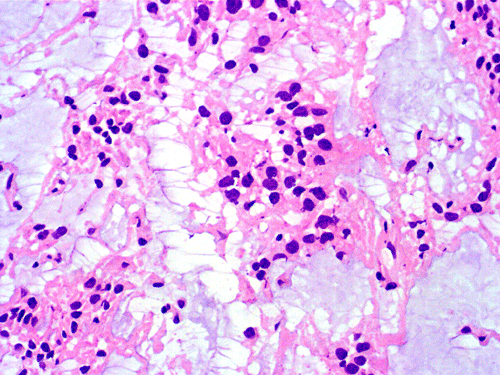

Clinical informationThe patient was a 40 year-old man with back pain for a long but unknown duration of time. MRI revealed a sharply circumscribed, lobulated, brightly enhancing, 3 cm mass in the cauda equina. The mass was removed and the followings are representative photomicrographs from the specimen. Panel A to C are taken from intraoperative cytologic preparation, D and E are taken from frozen section, F to H are taken from permanent sections.

On cytologic preparations, there are clumps of tissue that do not smear out well (Panel A). On higher magnification, these tissue clusters are composed of large blobs of bluish, acellular, mucoid material admixed with cells with relatively uniform, bland nuclei and small amount of cytoplasm (Panel B). In the less tightly packed areas, the long cytoplasmic processes of the cells can be well appreciated (Panel C). These long processes are highly suggestive of a glial neoplasm. On frozen sections, the lesion is composed of multiple blobs of bluish, mucoid material surrounded by tumor cells (Panel D and E). Features of the paraffin sections are not that much different from that of the frozen sections (Panel F G H).

Histopathology: The salient feature of myxopapillary ependymomas is a rich, thin walled micropapillary bundle surrounded by a single of epithelium that varies from low cuboidal to columnar. The cells typically have rounded nuclei with a delicate, rather open chromatin and a moderate amount of amphophilic cytoplasm. The cores of the papillae consist of blood vessels surrounded by a variable amount of mucinous matrix. The amount varies from small to substantial. The vessels are characterized by extensive thickening and hyalinization of the vessel wall. Ins some tumors, there are components with features of conventional ependymomas 24. Mitotic activity is very low or absent 25. Myxopapillary ependymomas usually have sharply defined margins, although nerve roots may be enclosed. A proportion of tumors are surrounded by a condensed connective tissue capsule 11.